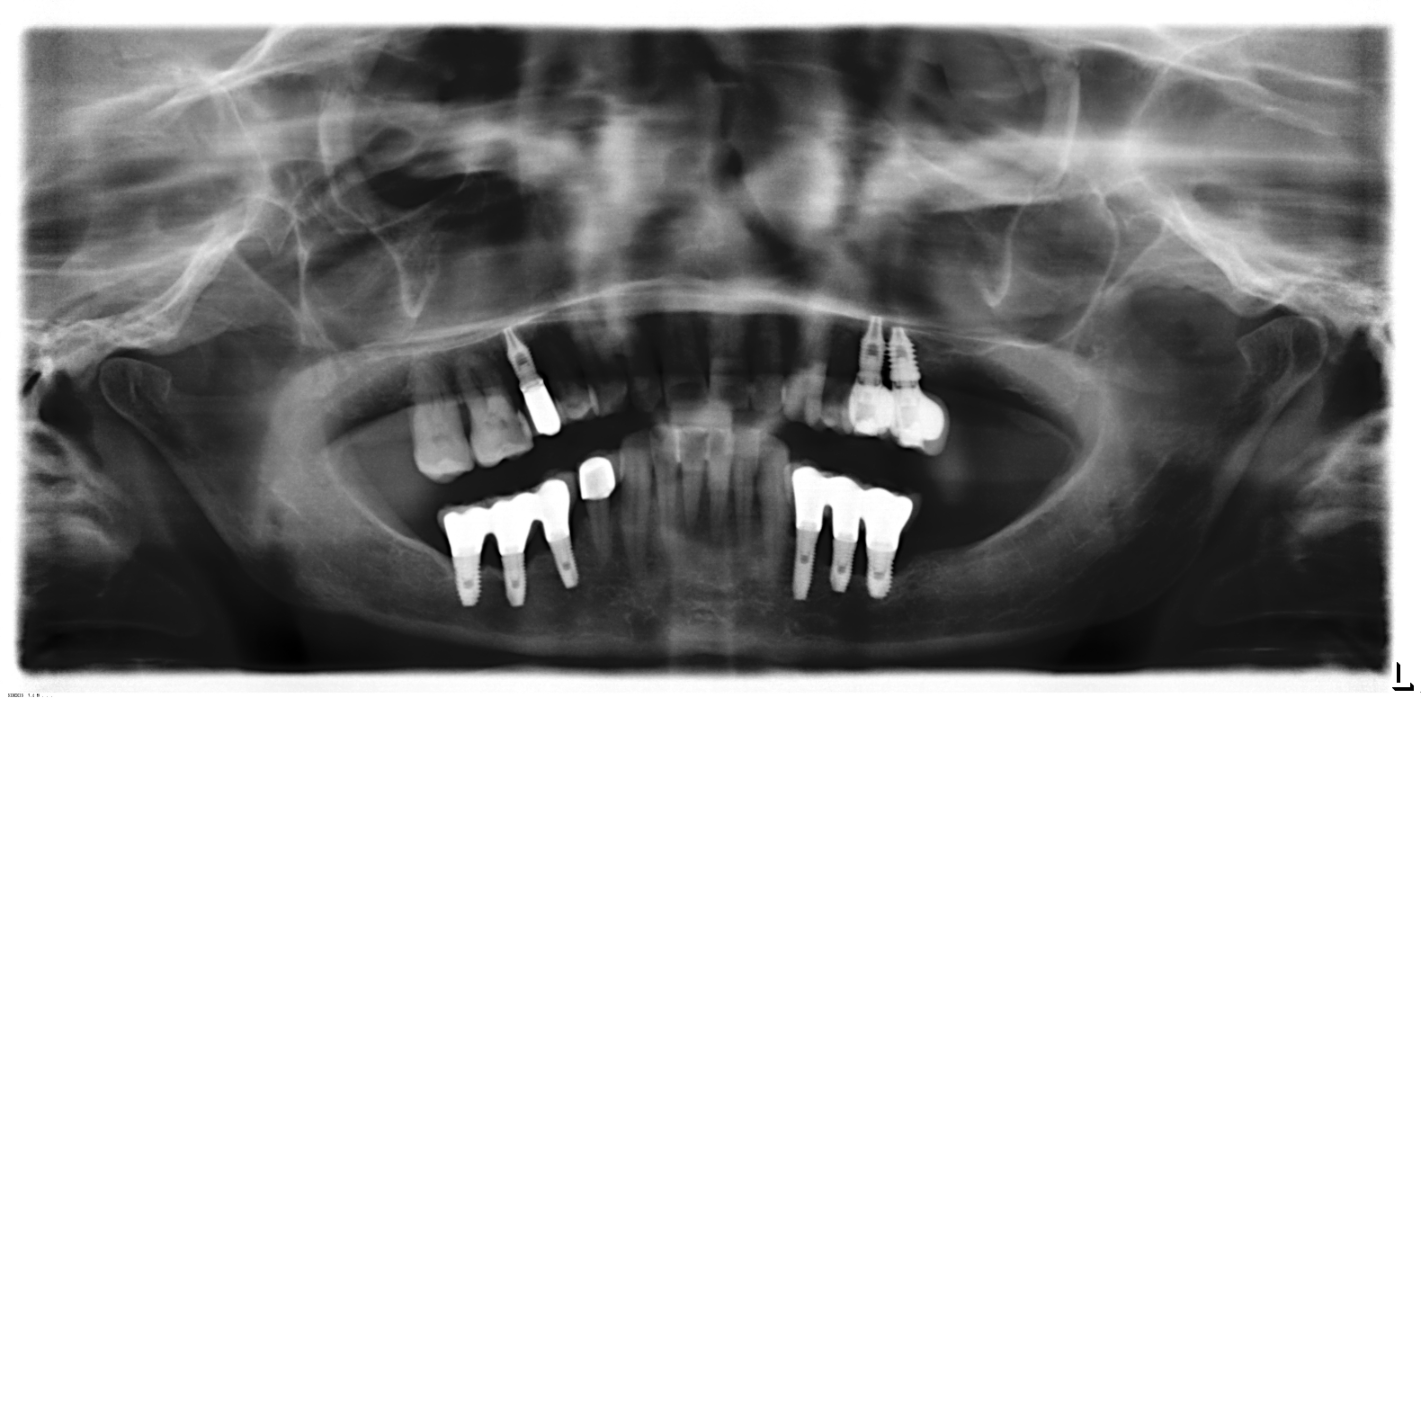

Buenas tardes compañeros, Paciente que acude a la clínica con movilidad sobre corona cementada sobre implante 27. Tras hacer la ventana de acceso consigo llegar al tornillo del pilar que [...]

Buenas compañeros: IOI colocado en Madrid en Febrero de este año. La clínica ha cerrado sin dar señales de vida. Me han chivado que podría ser un BIO Horizon de [...]